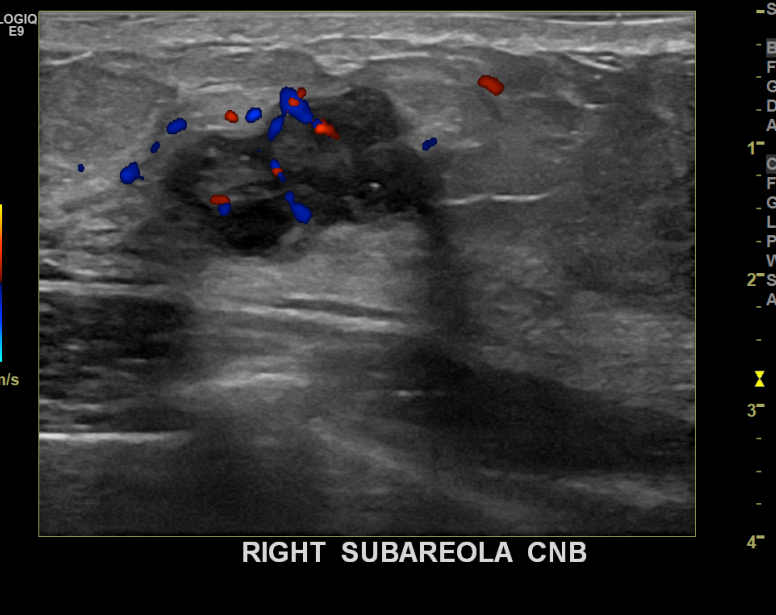

아산유외과 개원후 754번째 유방암진단

상기환자 검진상이상소견으로 내원하신 50대 여성분으로 우측 조직검사 시행후

유방암 진단되셨습니다.